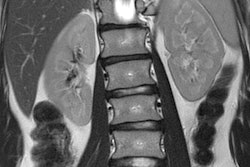

Scan time has been dramatically reduced, across various protocols, though focus has been directed mostly toward the highest-volume scans: spinal, brain, and knee. In many cases, the common scan time has been reduced by half or more, with new technology allowing protocols to run simultaneously. Expect such advances to spread into other more common protocols, with abdominal imaging next in line. Reduced scan time has benefits for patients and providers alike; shorter scans reduce patient anxiety and time in the scanner, as does noise reduction and new coil technology, while making MRI more available to patients. For providers, new systems allow an increase in patient throughput without comprising the quality of diagnoses, not to mention the financial and operational benefits. When considering also that analytics and business intelligence is increasingly being deployed to help manage and optimize patient scheduling and imaging practice management, we should expect that the newest generation of scanners will be the most accessible to patients yet.